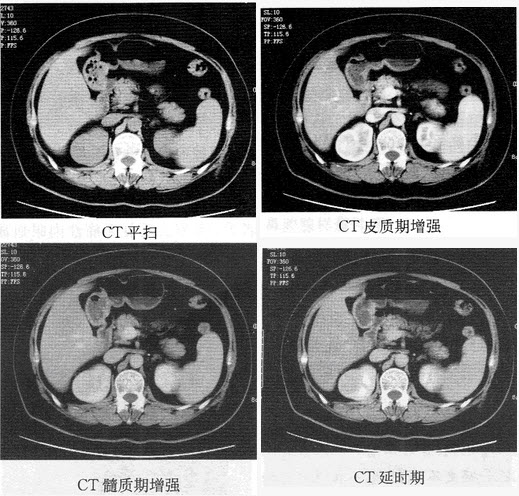

�����У�66�ꡣ������ʹ������Ѫ��3�ܣ�CTͼ�����£����п��ܵ�����ǣ���